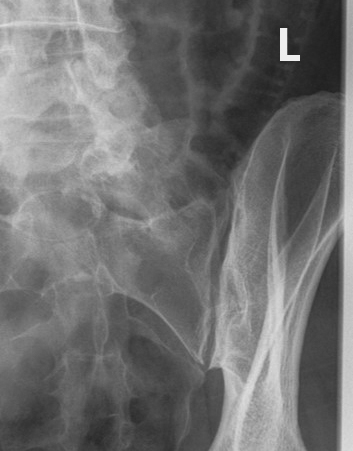

What are Judet views used for?

Evaluation of acetabular fractures.

<p>Evaluation of acetabular fractures.</p>

What is the patient position for an internal oblique Judet view?

Affected side raised 45°.

<p>Affected side raised 45°.</p>